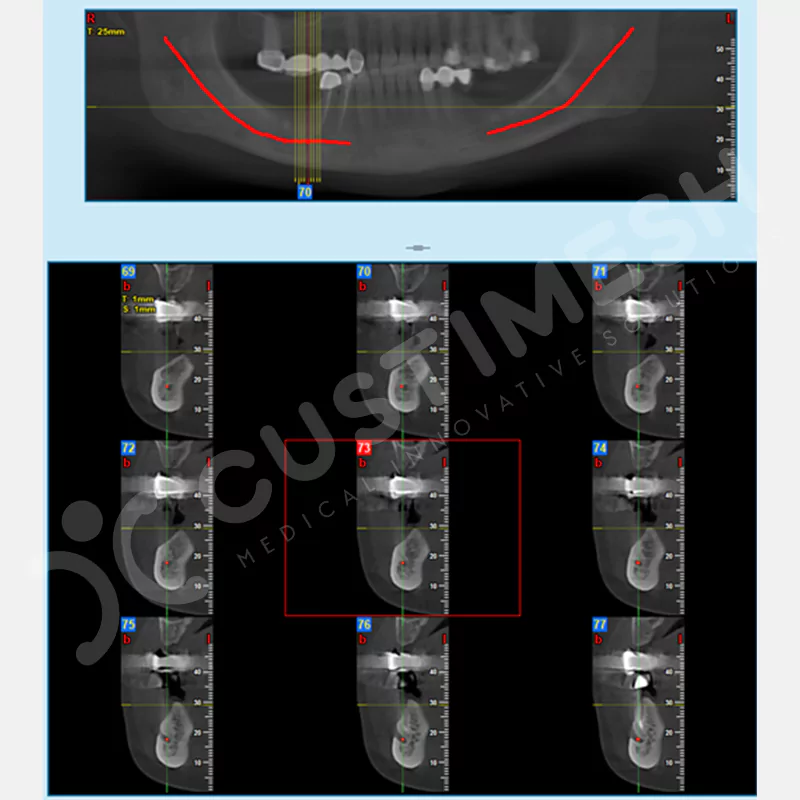

VAKA 2